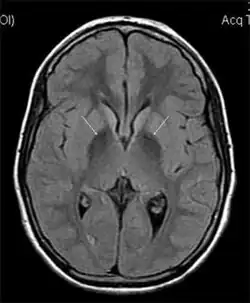

| MRI hypointensity (white arrows) in the globus pallidi that indicates the presence of iron deficiencies which would be seen in a diagnosis of Aceruloplasminemia | |

Diagnosis of this disorder depends on blood tests demonstrating the absence of serum ceruloplasmin, combined with low serum copper concentration, low serum iron concentration, high serum ferritin concentration, or increased hepatic iron concentration. MRI scans can also confirm a diagnosis; abnormal low intensities can indicate iron accumulation in the brain.[5]